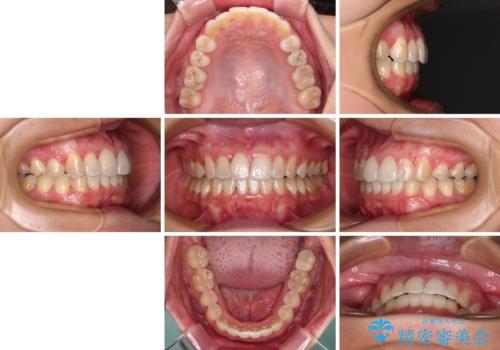

前歯のデコボコをインビザラインでスッキリと仕上げる

- 上下前歯のデコボコと奥歯の銀歯を気にして来院された患者様です。

口元をインビザラインにより歯列を整え、その後に失活している奥歯をオールセラミッククラウンにて補綴治療することとしました。

長時間のマウスピース装着に協力いただき、自然な口元に仕上げることができました。

気になっていた銀歯もオールセラミッククラウンで本物の歯のようになり、患者様には大変満足していただきました。